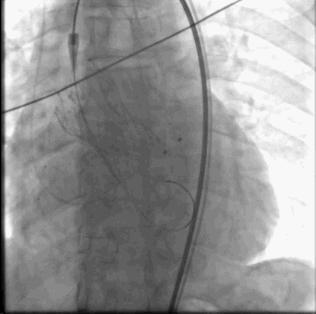

术中常规肝素抗凝。选取右侧股动脉为主路,穿刺左侧股动脉指引右侧行微穿刺,植入18F血管鞘。穿刺右侧颈内静脉植入右心室心尖临时起搏器。完成主动脉根部测压126/66mmHg,行主动脉根部造影。使用5F JR4导管带直头导丝成功跨瓣。交换猪尾导管测左室压力209/2mmHg。交换超硬导丝入左室,沿导丝送入CVB23*45mm球囊跨主动脉瓣,右室超速起搏180bmp,球囊扩展主动脉瓣并行主动脉根部造影评估球扩效果及冠脉风险。提示右冠脉显影欠佳,穿刺右侧桡动脉植入6F血管鞘,送JR4 GC至右冠脉口,沿GC送runthrough导丝至右冠脉远端,沿导丝送maverick2.0*20mm球囊至右冠脉内保护。沿加硬导丝送入VENUS A 29瓣膜及输送系统成功跨瓣,以左侧股动脉猪尾导管送至主动脉窦底部做标记,右室超速起搏120bmp,精准定位并释放瓣膜,期间反复猪尾造影确定瓣膜位置,撤出输送系统。复测主动脉根部压力125/55mmHg,左室心尖:125/10mmHg,主动脉根部造影左右冠显影清晰。在造影下缓慢退出股动脉长鞘,缝合并加压包扎双侧股动脉,术闭。

瓣膜释放

瓣膜释放完成左右冠显影良好撤出保护